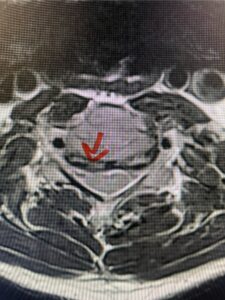

In this next case, this patient is a 47 year-old female who presents with intractable low back pain with severe pain, numbness, and weakness in the right lower extremity that had gotten progressively worse over a year. The patient had failed conservative management including physical therapy and epidurals. She was noted to have ⅘ weakness of plantar flexion. MRI demonstrated a large right L5-S1 disc herniation with severe compression of the descending right S1 nerve root (Fig 3). It was decided to perform a right L5-S1 hemilaminectomy for removal of the disc fragment and decompress the S1 nerve root. When you expose the disc, one must be certain to release any anterior adhesions to the nerve root in order to prevent a dural tear during retraction of the nerve root. It is also important to make sure during exposure and you finally encounter the dura after removing the ligamentum and fat, to make sure you are looking at the nerve root and not the main trunk of the thecal sac because if you don’t you can avulse or damage the nerve root if you retract the wrong structure.

Fig. 3a: Sagittal and axial T2-weighted lumbar MRI images demonstrating large right L5-S1 disc herniation (red arrows)

We found a massive subligamentous herniation which had to be revealed by having your partner retract the freed nerve root with a nerve root retractor and putting slight downward pressure on the more medial and anterior disc space. There is nothing more satisfying when the jelly (disc fragment) of the annulus (donut) comes squirting out and you remove a large chunk of disc material that clearly was stretching the ligament membrane and compressing the nerve root. This does cause back pain in addition to radiculopathy not only by the component of mechanical compression but also the stretching of the nerves within the ligament. We performed this surgery and noted that the nerve root was a very angry red color or hyperemic and we removed a large subligamentous fragment. The patient had improvement of her preoperative radicular symptoms.